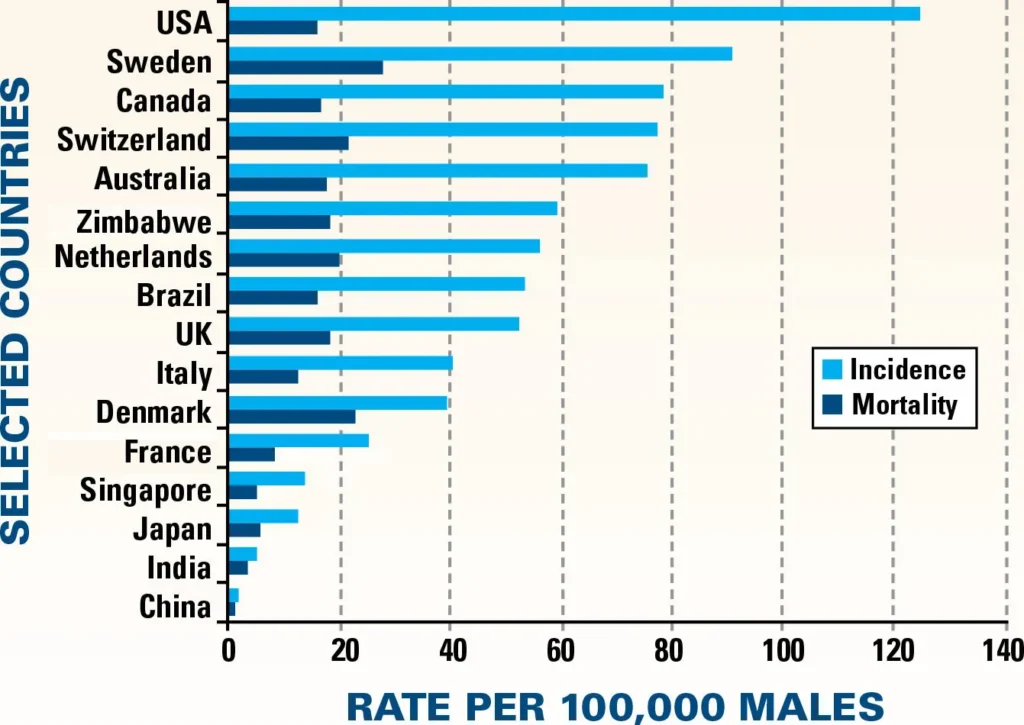

Problemas de Prostata no Mundo